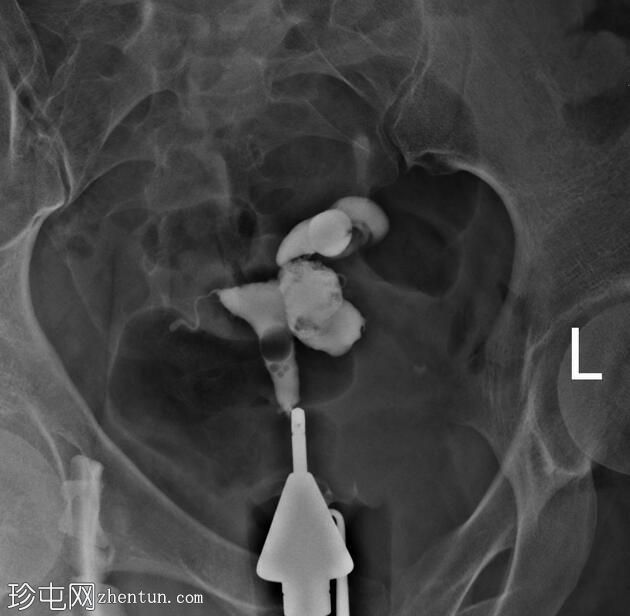

子宫位于盆腔正中线,形态及轮廓正常。

宫颈管长度及黏膜表面正常,扩张正常。

左侧输卵管充盈,管腔扩张,造影剂残留,无因输卵管积水导致的溢液。

右侧输卵管峡部造影剂显影中断,造影剂远端呈球状扩张。